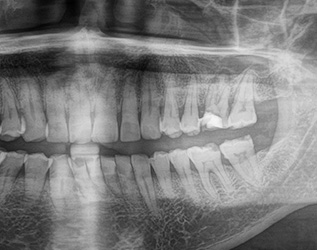

No. 22

임플란트와

틀니